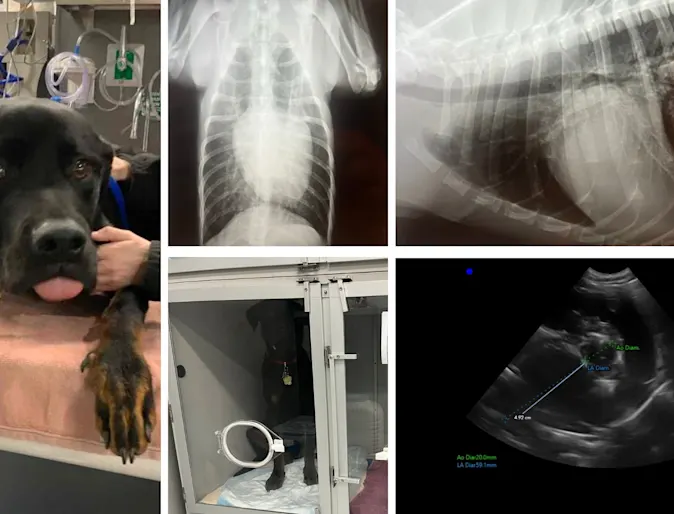

Roscoe, a 9-month-old Rottweiler, presented to his primary veterinarian when his owner noticed a strange breathing pattern.

Sternal Deviation